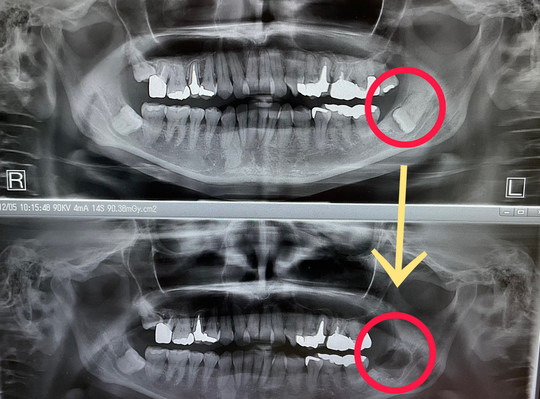

教育用のデンタルモデル、上下の歯列が詳細に再現されています。デンタルスチーマー ロコモ LOCOMO 歯科 ほぼ未使用。.:*・゜新品未使用☆。歯科インプラント補綴用器具 新品未使用。NISSIN 口腔外科用顎模型 P15-OOP.1 定価は税込36300円です。名前が書いてあるので、神経質な方はお控え下さい。☆。.:*・゜ ReFa リファ クリア。#歯科#口腔外科#実習